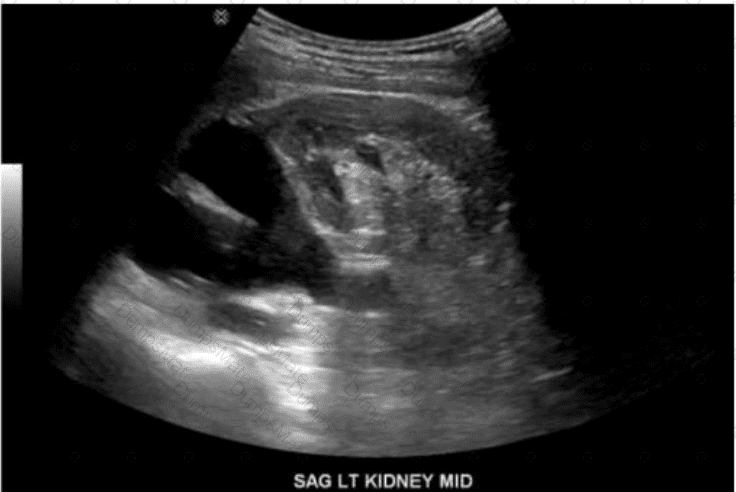

Which renal anomaly is demonstrated on this image?

AB-Abdomen Question 24

Options:

A.

Duplicated collecting system

B.

Crossed renal ectopia

C.

Horseshoe kidney

D.

Pelvic kidney

Buy Now